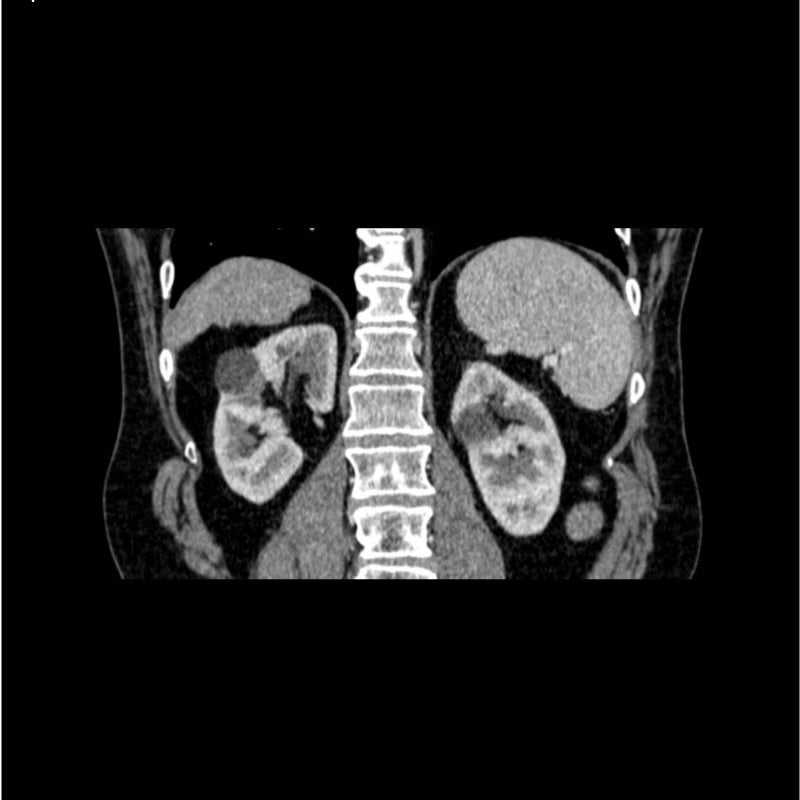

abdomen in portal venous phase. It covers the tenth thoracic vertebra to the third lumbar vertebra. The phantom represents an abdomen after cholecystectomy with small clips. The liver has typical signs of cirrhosis and there is an inferior vena cava filter implanted at the level of the third lumbar vertebra. Both kidneys have cystic lesions and there is a small kidney stone on the left side.

Realistic simulation of vasculature, bone and soft tissues, including the liver, pancreas, spleen, adrenals, kidneys, stomach, small intestine and colon.

- Liver cirrhosis

- cholecystectomy

- inferior vena cava filter

- kidney cysts

- kidney stone

- lymph nodes.